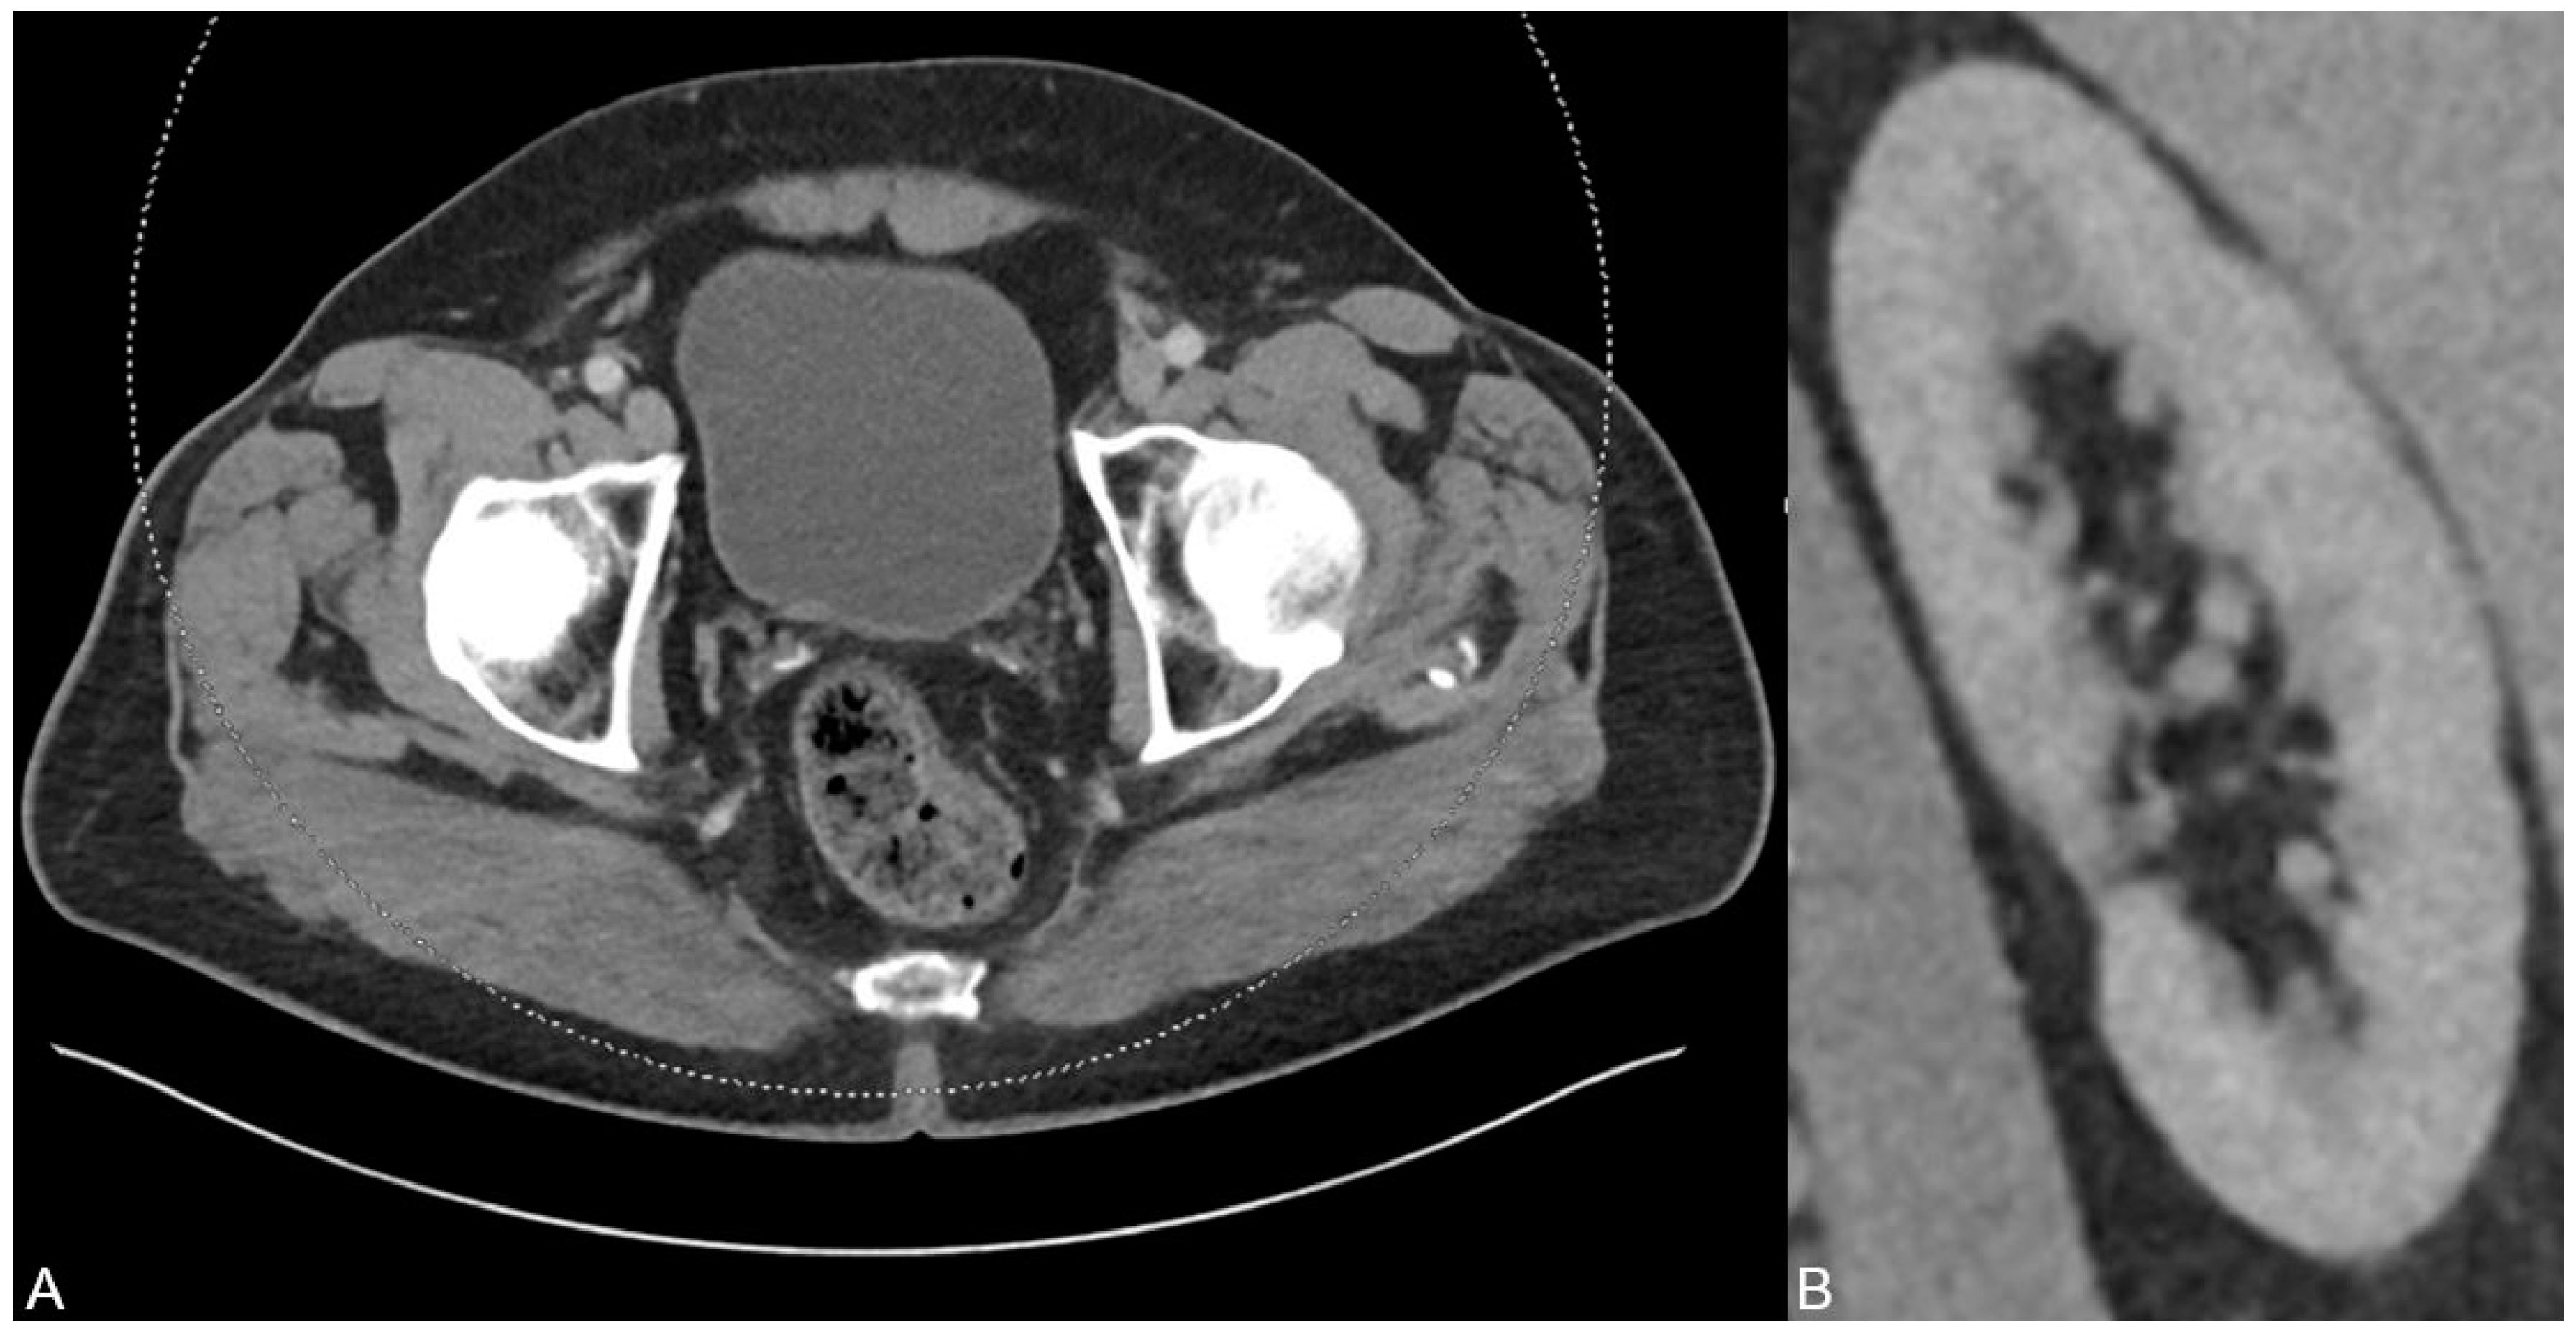

A 70-year old man was presented to our emergeny department with acute left-sided strong flank pain and clearing of fragments since some weeks ago. The only known diseases included polycythaemia vera and actinic keratosis. The polycythaemia vera was treated with aspirin and ruxolitinib (janus kinase inhibitor). The initial body check showed no signs of hematoma or inflammation. The abdomen was soft during palpation, and the pain was not influencable during the check. Laboratory blood values showed no signs of infection or ischemia. The urinary pH was 5.1. Besides the urinary pH, all other urinary tests/values (no microhematuria and no elevated leucocyte levels) were inconspicuous. The initially performed ultrasound examination revealed no presence of any acute bowel pathology including appendicitis or diverticulitis or any presence of an urinary stone. Due to the persistent strong pain, a monophasic CT scan was performed in the portal venous phase on a third-generation dual-source dual-energy CT scanner (SOMATOM Force, Siemens Healthineers, Forchheim, Germany) to check for any missed pathologies. The CT scan protocol represents a standard protocol at our institution consisting of a scan 70 s after contrast material injection (Iomeron 400 mg, injected at a dose of 1.3 mL per kilogram body weight and at a flow rate of 2 mL/s through a superficial vein of the forearm) using a dual-energy mode with tube voltages of 90 and 150 kV due to the known several advantages of dual-energy CT in clinical routine [1,2,3,4,5,6,7,8,9]. The scan revealed a known splenomegaly but no signs of a splenic rupture or infarction (A). In addition, no free fluid was present. Instead, a second grade urinary stasis in the left kidney (B) and hyperdense material in the bladder adjacent to the posterior wall in terms of an urine sedimentation (C) were noted. Although there was no sign of an ureter obstruction by the sediment, the sediment was the only finding which may have caused decreased flow and corresponding stasis in the CT scan. No other acute pathologies were present in this scan.